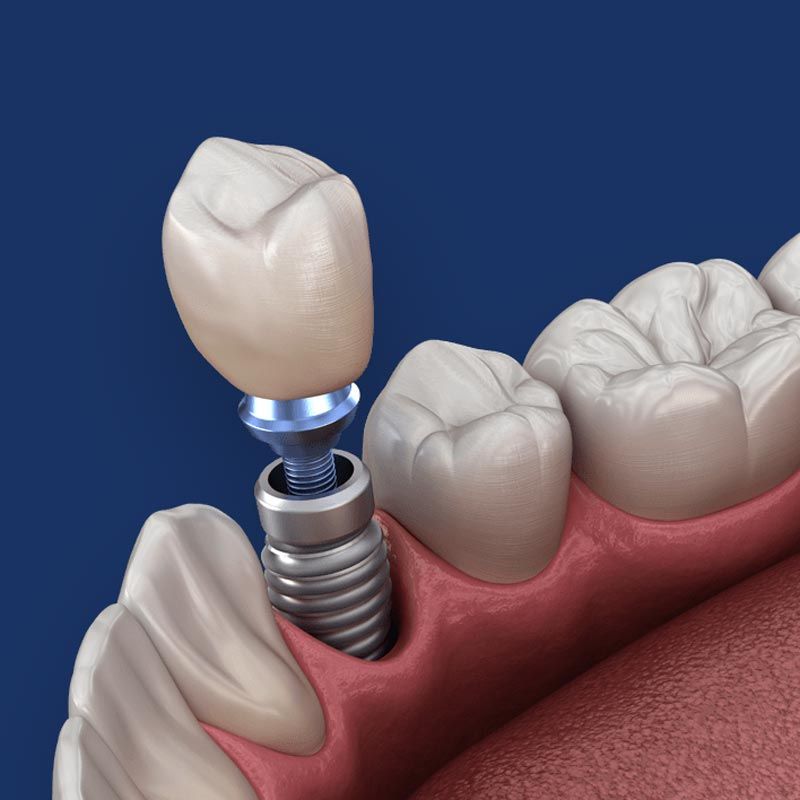

Because implants are priced separately, the number you receive will be one of the most significant factors affecting the cost of your treatment. Typically, you will need one for a crown, two or more for a bridge, and four or more for a denture. Each dental implant requires an abutment (a device that connects the implant to the restoration).

Type of Restoration

The type of implant-supported restoration you need will affect the cost of your treatment. Larger dental restorations like full dentures will usually carry a higher price than a single crown. Additionally, the restorative material you choose can affect the cost. For example, state-of-the-art zirconia will cost more than standard porcelain.